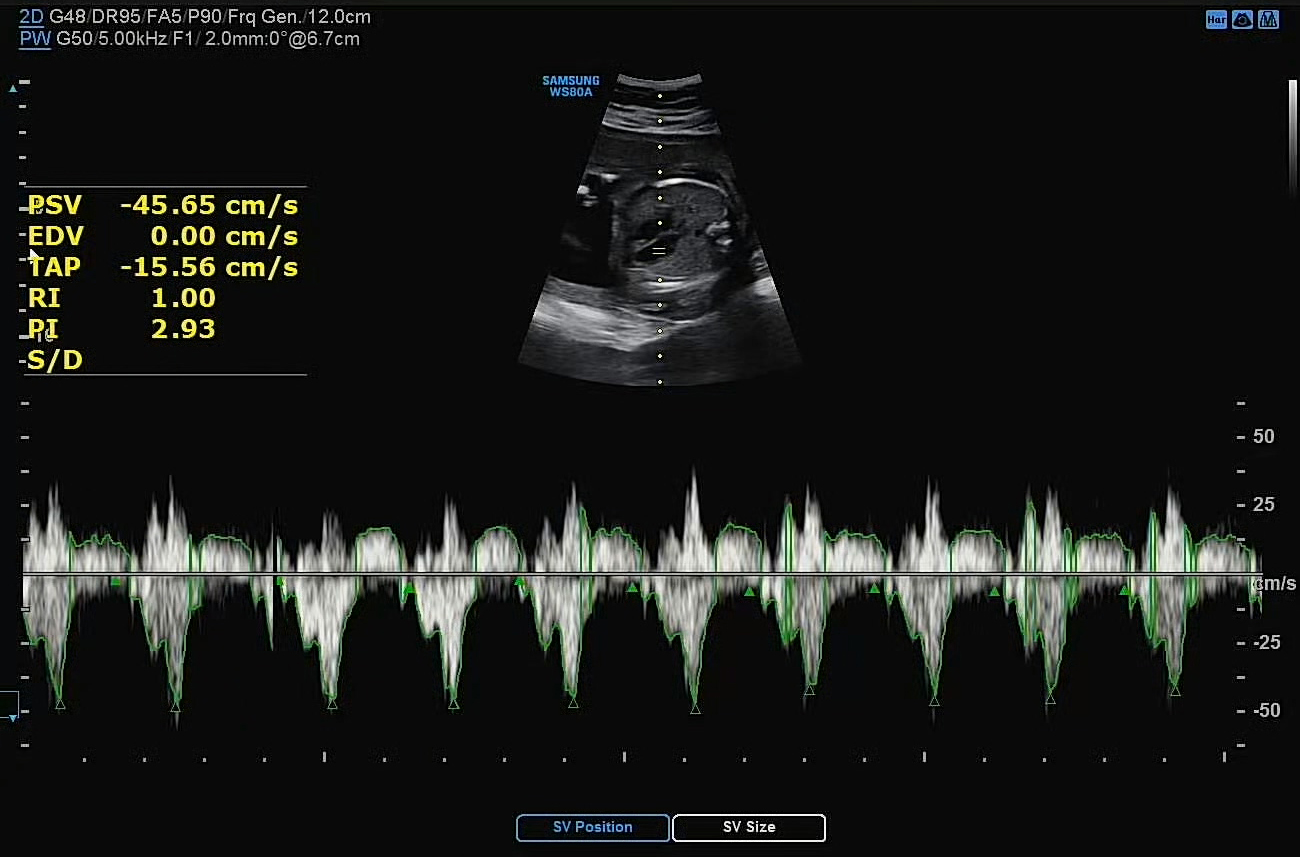

척수 발달, 폐 발달, 심장도 좌심실, 우심실 등 각 기관이 성인처럼 세분화되어 발달되고 있는 것을 선생님이 꼼꼼히 체크해주셨다. 다행히 아내의 양수도 평균치 정도 있고, 자궁 경부 길이도 정상이라 조산 기미 없이 안전하다고 하였다.